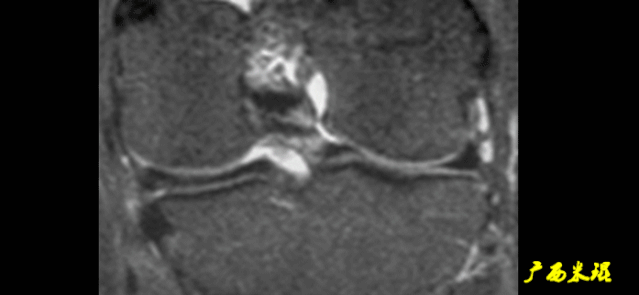

2)骨挫伤:

一旦ACL撕裂,胫骨就相对于股骨前移,使股骨外侧髁和胫骨外后方撞击,双方均出现水肿,而且膝关节屈曲的程度决定股骨髁挫伤的部位。

3)沟槽征:

当股骨外髁骨因撞击造成的凹陷深度>2mm时称为沟槽征,代表受到撞击的暴力更大。

4)接吻征:

A.膝关节过伸受伤时,胫骨前部撞击股骨髁前部,形成对称性骨挫伤。

B.如果同时有一外翻力的话,膝关节外侧可出现对称性挫伤,这种对称性骨挫伤称为接吻征。

C.也有人把轴移造成的股骨外侧髁和胫骨外后方水肿称为接吻征。